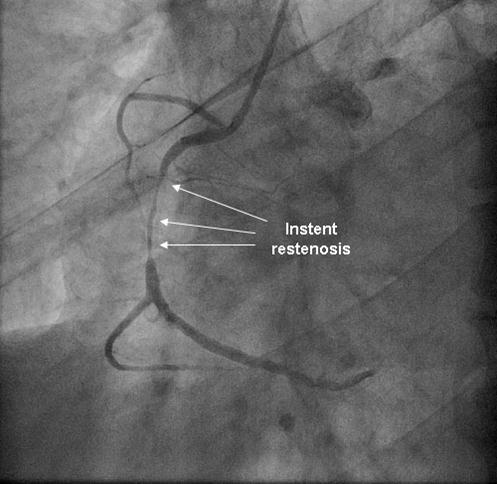

Coronary angiography was again performed. On injections into the left system, collaterals to the distal RCA were demonstrated (figure 1), arising from the left circumflex coronary artery (CX). Injections into the RCA demonstrated tight in-stent restenosis, (figure 2) and a drug eluting stent was successfully implanted. After the angioplasty, injections into the RCA were seen to retrogradely fill the CX (figure 3). The suspicion arose that maybe the left coronary artery had been inadvertently damaged during angiography, so the left coronary was again cannulated and injections performed, demonstrating entirely normal left main and CX arteries. However, the collateral flow that had previously been demonstrated from the CX to the RCA was no longer apparent. On review of the previous angiogram, it was noted that the RCA retrogradely filled the CX despite the original significant stenosis (figure 4). In essence, it became apparent that the bidirectional filling of the RCA from the CX and vice versa was in fact a direct continuity between the vessels and not collaterals, as free flow was noted from the RCA to the CX even when both arteries were completely patent.

Figure 2.Instent restenosis in proximal RCA

Instent restenosis in proximal RCA